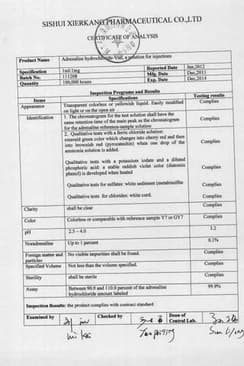

Состав препарата Адреналина гидрохлорид-Виал

Раствор для инъекций1 мл

эпинефрин (в форме гидрохлорида) 1 мг

Сертификаты